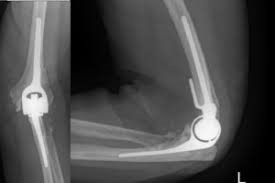

Ολική αρθροπλαστική αγκώνα

Πότε επιλέγεται η ολική αρθροπλαστική του αγκώνα;

Ο αγκώνας είναι η άρθρωση που ενώνει το μπράτσο με τον πήχη μας, άρθρωση σημαντική για την καθημερινή δραστηριότητα μας ακόμα και για απλές πράξεις, όπως είναι το να κουβαλήσουμε μια τσάντα. Ευτυχώς δεν προσβάλλεται συχνά από καταστροφική οστεοαρθρίτιδα. Όμως είναι από τις αρθρώσεις που προσβάλει συχνά -περίπου στο 20% των πασχόντων- η ρευματοειδής αρθρίτιδα, μια αρθρίτιδα αυτοάνοσης αιτίας. Είναι επίσης μια άρθρωση επιρρεπής σε συντριπτικά κατάγματα ανεπίδεκτα χειρουργικής θεραπείας σε οστεοπορωτικούς ασθενείς.

Μέχρι πριν από λίγες δεκαετίες μια ρευματοπάθεια ή ένα κάταγμα στην περιοχή του αγκώνα θα είχε ως αποτέλεσμα μόνιμη αναπηρία ή χρόνιο πόνο και δυσλειτουργία. Όμως πλέον μπορεί να γίνει αντικατάσταση της άρθρωσης με μηχανικά μέρη που εξυπηρετούν πλήρως τη φυσιολογική λειτουργία του αγκώνα. Η αύξηση του αριθμού τέτοιων επεμβάσεων σε ηλικιωμένα άτομα με συντριπτικά κατάγματα του αγκώνα είναι εντυπωσιακή.